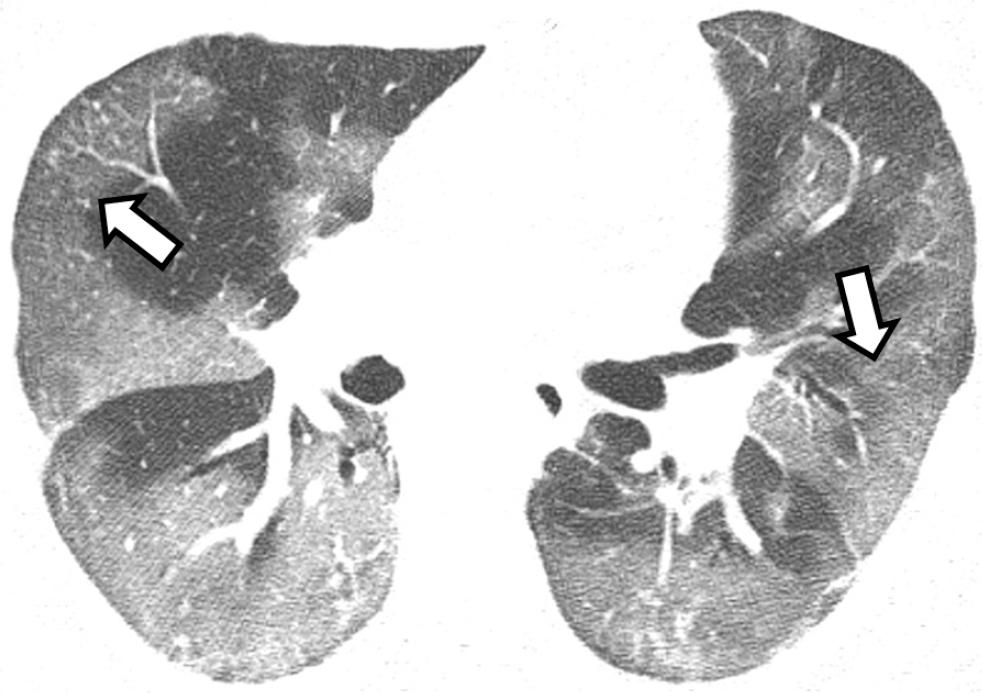

En la tomografía simple de tórax realizada al ingreso de cada paciente, los patrones más comunes fueron los siguientes: opacidad de vidrio esmerilado de predominio periférico y subpleural (Figura 1), encontrado en 15.9 % de los hombres y 20 % de las mujeres; la consolidación, con predominio hacia los segmentos posterobasales (Figura 2); así como los patrones de empedrado y mixto, forma concomitante de los mencionados (Figura 3). En los diagramas de Venn (Figura 4) se representan los porcentajes de las diferentes combinaciones de patrones.

Figura 1 Hombre de 83 años con neumonía causada por SARS-CoV-2 de dos días de evolución. Se observa patrón de vidrio esmerilado de predominio periférico (flecha larga).